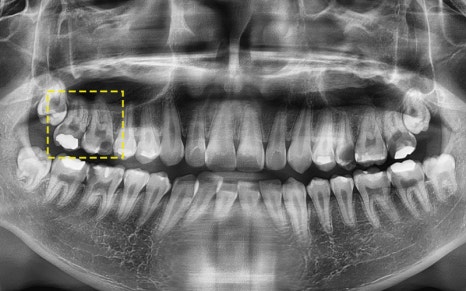

🔷 가장 좋은 임플란트를 선택한 환자분 이야기

2025.05.25

이 환자분은 고작 19세입니다.

어린 나이에 충치로 인해 어금니를 잃고,

임플란트 치료를 결심하게 되었는데요.

하지만 이 환자분에게는

특별한 고민이 필요했습니다.

“아직 너무 어리다.

앞으로 이 임플란트를 수십 년 써야 한다.”

2025.05.31

그래서 저희는 세계에서 가장 오래 쓰이는,

그리고 가장 튼튼하다고 인정받는

스위스 스트라우만 임플란트를 추천드렸고

수술을 진행하였습니다!